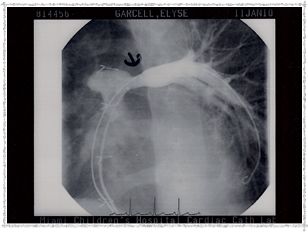

Second Catheterization — Dr. Danyal Khan

In 2010, Elyse underwent her second catheterization procedure, overseen by Dr. Danyal Khan at Miami Children's Hospital. The procedure focused on her pulmonary arteries, and these images show the before and after.

2010 - Left Pulmonary Artery After

Left Pulmonary Artery — After